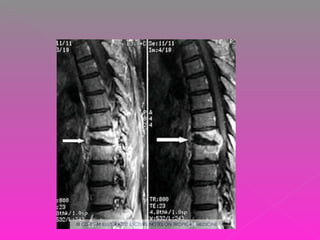

 LA PACIENTE CUENTA CON UNA TAC QUE

REPORTA:

 CUERPO DE T9, CON IMÁGENES

OSTEOLÍTICAS, EXPANSIVAS Y DE PATRÓN

DIFUSO QUE INVADEN CANAL NEURAL EN

UN 50% APROX. ASÍ MISMO HAY LISIS EN

PLATAFORMAS SUPERIOR E INFERIOR Y

PARED ANTERIOR. NO SE OBSERVAN

LESIONES ASOCIADAS.

 DESTRUCCIÓN VERTEBRAL POR PROCESO

TUMORAL SECUNDARIO VS PROCESO

INFECCIOSO.

 INSTRUMENTACIÓN POSTERIOR DE T6-T7 A

T10-T11 MÁS DESCOMPRESIÓN

POSTERIOR, TOMA DE BIOPSIA DE

CUERPOS VERTEBRALES T8, T9.

 CORPECTOMIA T8,T9 Y SUSTITUCIÓN DE

COLUMNA ANTERIOR CON INJERTO ÓSEO

AUTÓLOGO DE CIIZQ.